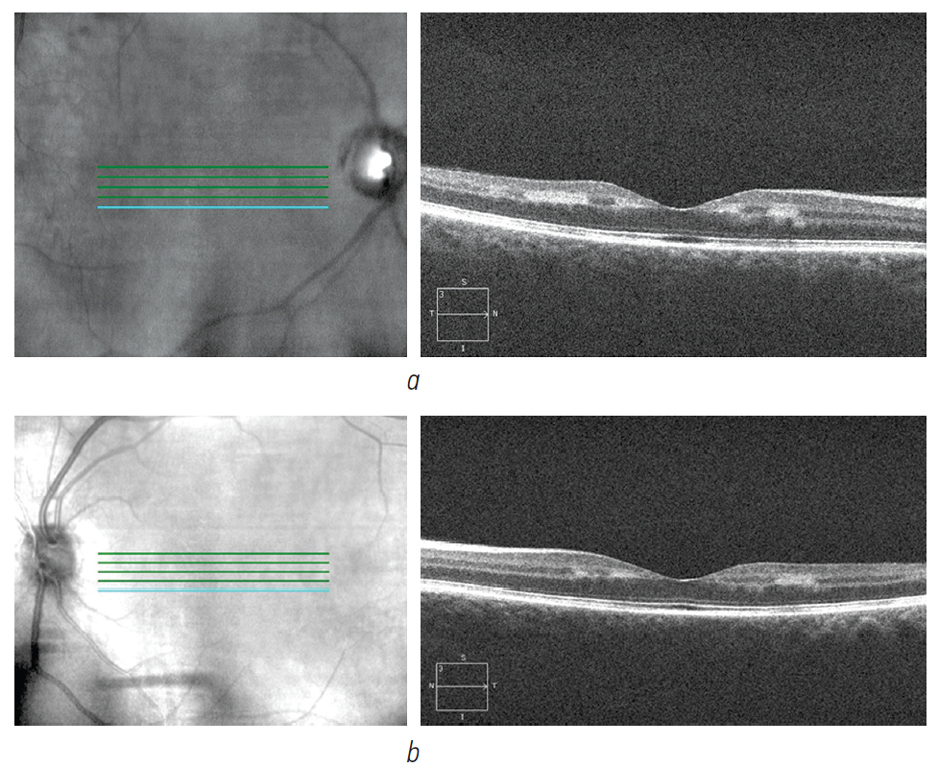

На ОКТ-снимках, выполненных в стационаре на момент поступления, были выявлены множественные гиперрефлективные очаги на уровне внутреннего ядерного, наружного и внутреннего плексиформных слоёв, разреженность в слое наружных сегментов фоторецепторов (рис. 7). Представленная ОКТ-картина соответствовала «диффузному» паттерну ПОСМ, так как в ишемический процесс вовлекаются все три слоя: внутренний ядерный и прилежащие плексиформные слои. «Диффузный» паттерн ПОСМ свидетельствовал о более грубых перфузионных нарушениях в глубоком сосудистом сплетении и о возможном переходе в хронический ишемический процесс. Поражения ОМН затронули наружную часть сетчатки и проявлялись разрежённостью наружных сегментов фоторецепторов.

Рис. 7. ОКТ-сканирование правого (а) и левого (b) глаза после травмы

Fig. 7. OCT-scans of the right eye (a) and of the left eye (b) after injury

На ОКТ на обоих глазах визуализируется сглаженность макулярного профиля, неравномерность внутренних слоёв сетчатки, гиперрефлективные включения во внутренних слоях сетчатки, а также гиперрефлективная зона с чёткими краями во внутреннем плексиформном слое на правом глазу (рис. 9). На местах «диффузного» паттерна ПОСМ визуализируются обширные зоны атрофии внутреннего ядерного и наружного плексиформного слоёв, которые стали результатом хронической ишемии на уровне глубокого капиллярного сплетения, о чём свидетельствует локально сохраняющая гиперрефлективность на уровне плексиформных слоёв. На уровне фоторецепторов повреждений нет.

Рис. 9. ОКТ-сканирование правого (а) и левого (b) глаза

Fig. 9. OCT-scans of the right eye (a) and of the left eye (b)